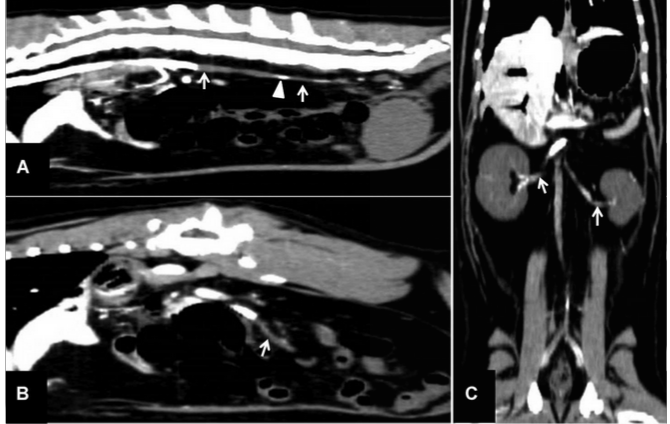

Multiple filling defects of the arterial system, including abdominal aorta, bilateral large infarcts to the kidneys as no contrast is present within them and cranial mesenteric artery.

Imaging diagnosis - Acute mesenteric ischemia secondary to HCM in a cat - VRU 56.4

Adult cat presenting for abdominal pain and dragging rear limbs.